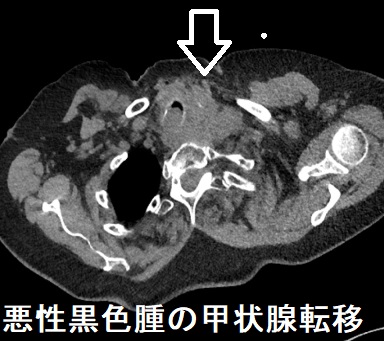

悪性黒色腫(メラノーマ)の甲状腺転移(転移性甲状腺癌(他臓器の癌から甲状腺への転移))

(Arch Endocrinol Metab. 2017 Mar-Apr;61(2):193-197.)(Ear Nose Throat J. 2009 Jan;88(1):E7.)

悪性黒色腫(メラノーマ)は顔よりも足の裏にできやすく、隆起はなく表面は平滑ですが、良性の黒子(ホクロ)と比べると、やや大きめで、形がいびつ、色合いがマダラです。

悪性黒色腫(メラノーマ)は濃淡のある褐色斑で、粗大で不規則な菱形構造の偽ネットワークを形成します。

悪性黒色腫(メラノーマ)と甲状腺乳頭癌の共通性;共通のBRAF V600E突然変異を有し、重複癌を発症するリスクが高い(Hum Pathol. 2013 Nov;44(11):2563-70.)

写真は、悪性黒色腫(メラノーマ)と甲状腺乳頭癌の重複癌(Ann Dermatol. 2010 Aug;22(3):370-2.)